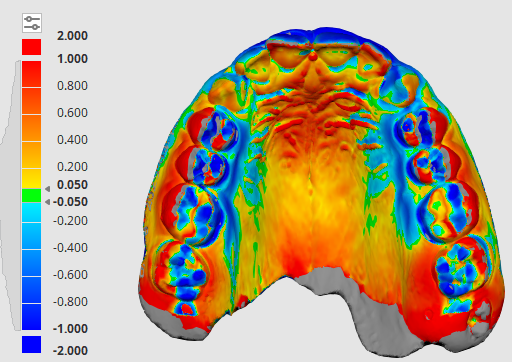

Adaptive Orthodontics Pre-Op Analysis – 2020-11-25 Age : 9 Class 2 div I and div IIMixed DentitionLower lip entrapment NORMALLY LOWER LIP ENTRAPPED BEHIND UPPER ANTERIOR NORMALLY LOWER LIP ENTRAPPED BEHIND UPPER ANTERIOR PROCLINE (OVERJET) UPPER ANTERIORDIASTEMA (SPACING) – TONGUE THRUSTLOWER LIP ENTRAPMENTNARROW (GOTHIC) ARCHDEEP BITE – SOFT TISSUE TRAUMA STAGE 1 RETRACT UPPER ANTERIORS… Read.